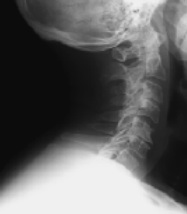

La radiografía ofrece información técnica relevante para la planificación quirúrgica y la resonancia magnética nos indica el grado de compromiso y los niveles afectados. En algunos casos, se solicitan pruebas neurofisiológicas para valorar la cronología del cuadro o ayudar a establecer el diagnóstico diferencial.